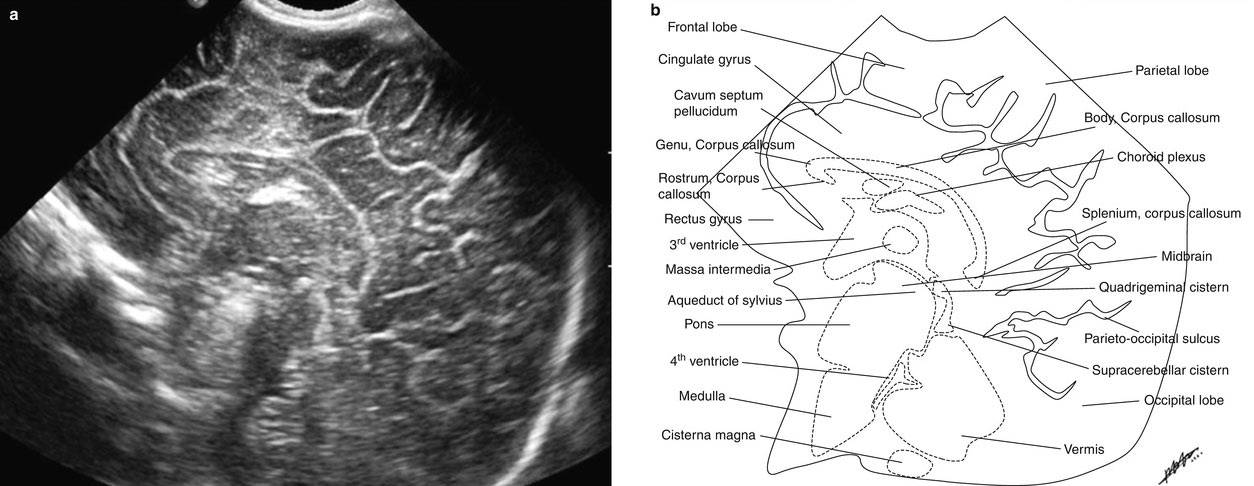

Рисунки: снимки и расположение структур мозга

Борозды и извилины коры мозга отражают степень его зрелости. Извилины полушарий активно дифференцируются с 28 недели беременности и становятся видны при УЗИ спустя 2-6 недель после того, как сформируются в анатомические структуры. После рождения ребенка локализация и количество борозд и извилин в норме соответствуют строению мозга взрослого человека.

Желудочковая система представлена четырьмя сообщающимися полостями, заполненными спинномозговой жидкостью. Боковые желудочки по мере увеличения срока беременности суживаются, становясь щелевидными, каковыми и остаются в норме и у ребенка, и у взрослого. Допускается некоторая асимметрия желудочков в пределах двух миллиметров на уровне отверстия Монро, которая считается вариантом нормы.

Расширение полостей боковых мозговых желудочков говорит о гидроцефалии, и начинается оно с задних рогов. С уверенностью говорить об увеличении желудочков можно в том случае, если размер передних рогов в области отверстия Монро становится более пяти миллиметров.

Сосудистые сплетения находятся в желудочковой системе и вырабатывают ликвор. Их не должно быть в передних и задних рогах боковых полостей, обычно они ровные, гладкие и симметричные, однако не считается патологией и некоторая шероховатость со слабой асимметричностью сосудов. Чем больше срок беременности, тем меньше становятся сплетения относительно объема желудочка. Несомненная патология в виде кровоизлияний в желудочки проявляется асимметрией и очаговым увеличением плотности сплетений, которые сменяются появлением кистозной полости.

Из всех отделов мозга наиболее удален от большого родничка мозжечок, поэтому он хуже всего просматривается при нейросонографии. В норме он должен иметь два сформированных полушария и червь, расположенный между ними. Поперечник мозжечка пропорционален диаметру головы плода, поэтому этот показатель может служить для определения срока беременности.

Нейросонографическая оценка состояния мозговой паренхимы включает анализ коркового слоя, толщина которого в норме не должна быть более нескольких миллиметров. Белое вещество отличается большей эхогенностью, нежели кора

Особое внимание уделяется так называемой перивентрикулярной (вокруг боковых желудочков) зоне, которая должна быть симметричной с обеих сторон, с нечеткими краями. Появление асимметрии или увеличение плотности этой области может говорить о возможной лейкомаляции, которая влечет неврологические проблемы у малышей. Например: